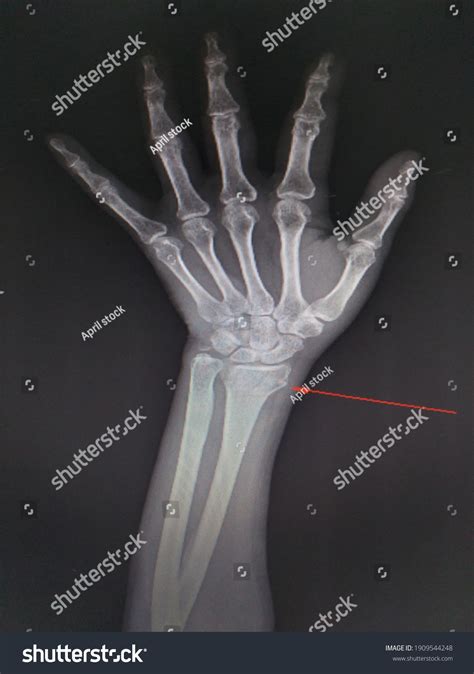

Imaging studies, such as X-rays, CT scans, and MRI, can provide detailed information about the Styloid Process Ulna and surrounding structures. These studies can help identify fractures, degenerative changes, and other abnormalities.

Fractures of the Styloid Process Ulna are relatively rare but can occur due to trauma, such as a fall on an outstretched hand or a direct blow to the wrist. These fractures can be challenging to diagnose due to their small size and the overlap of other bony structures on radiographs. However, they can cause significant pain and instability in the wrist joint.